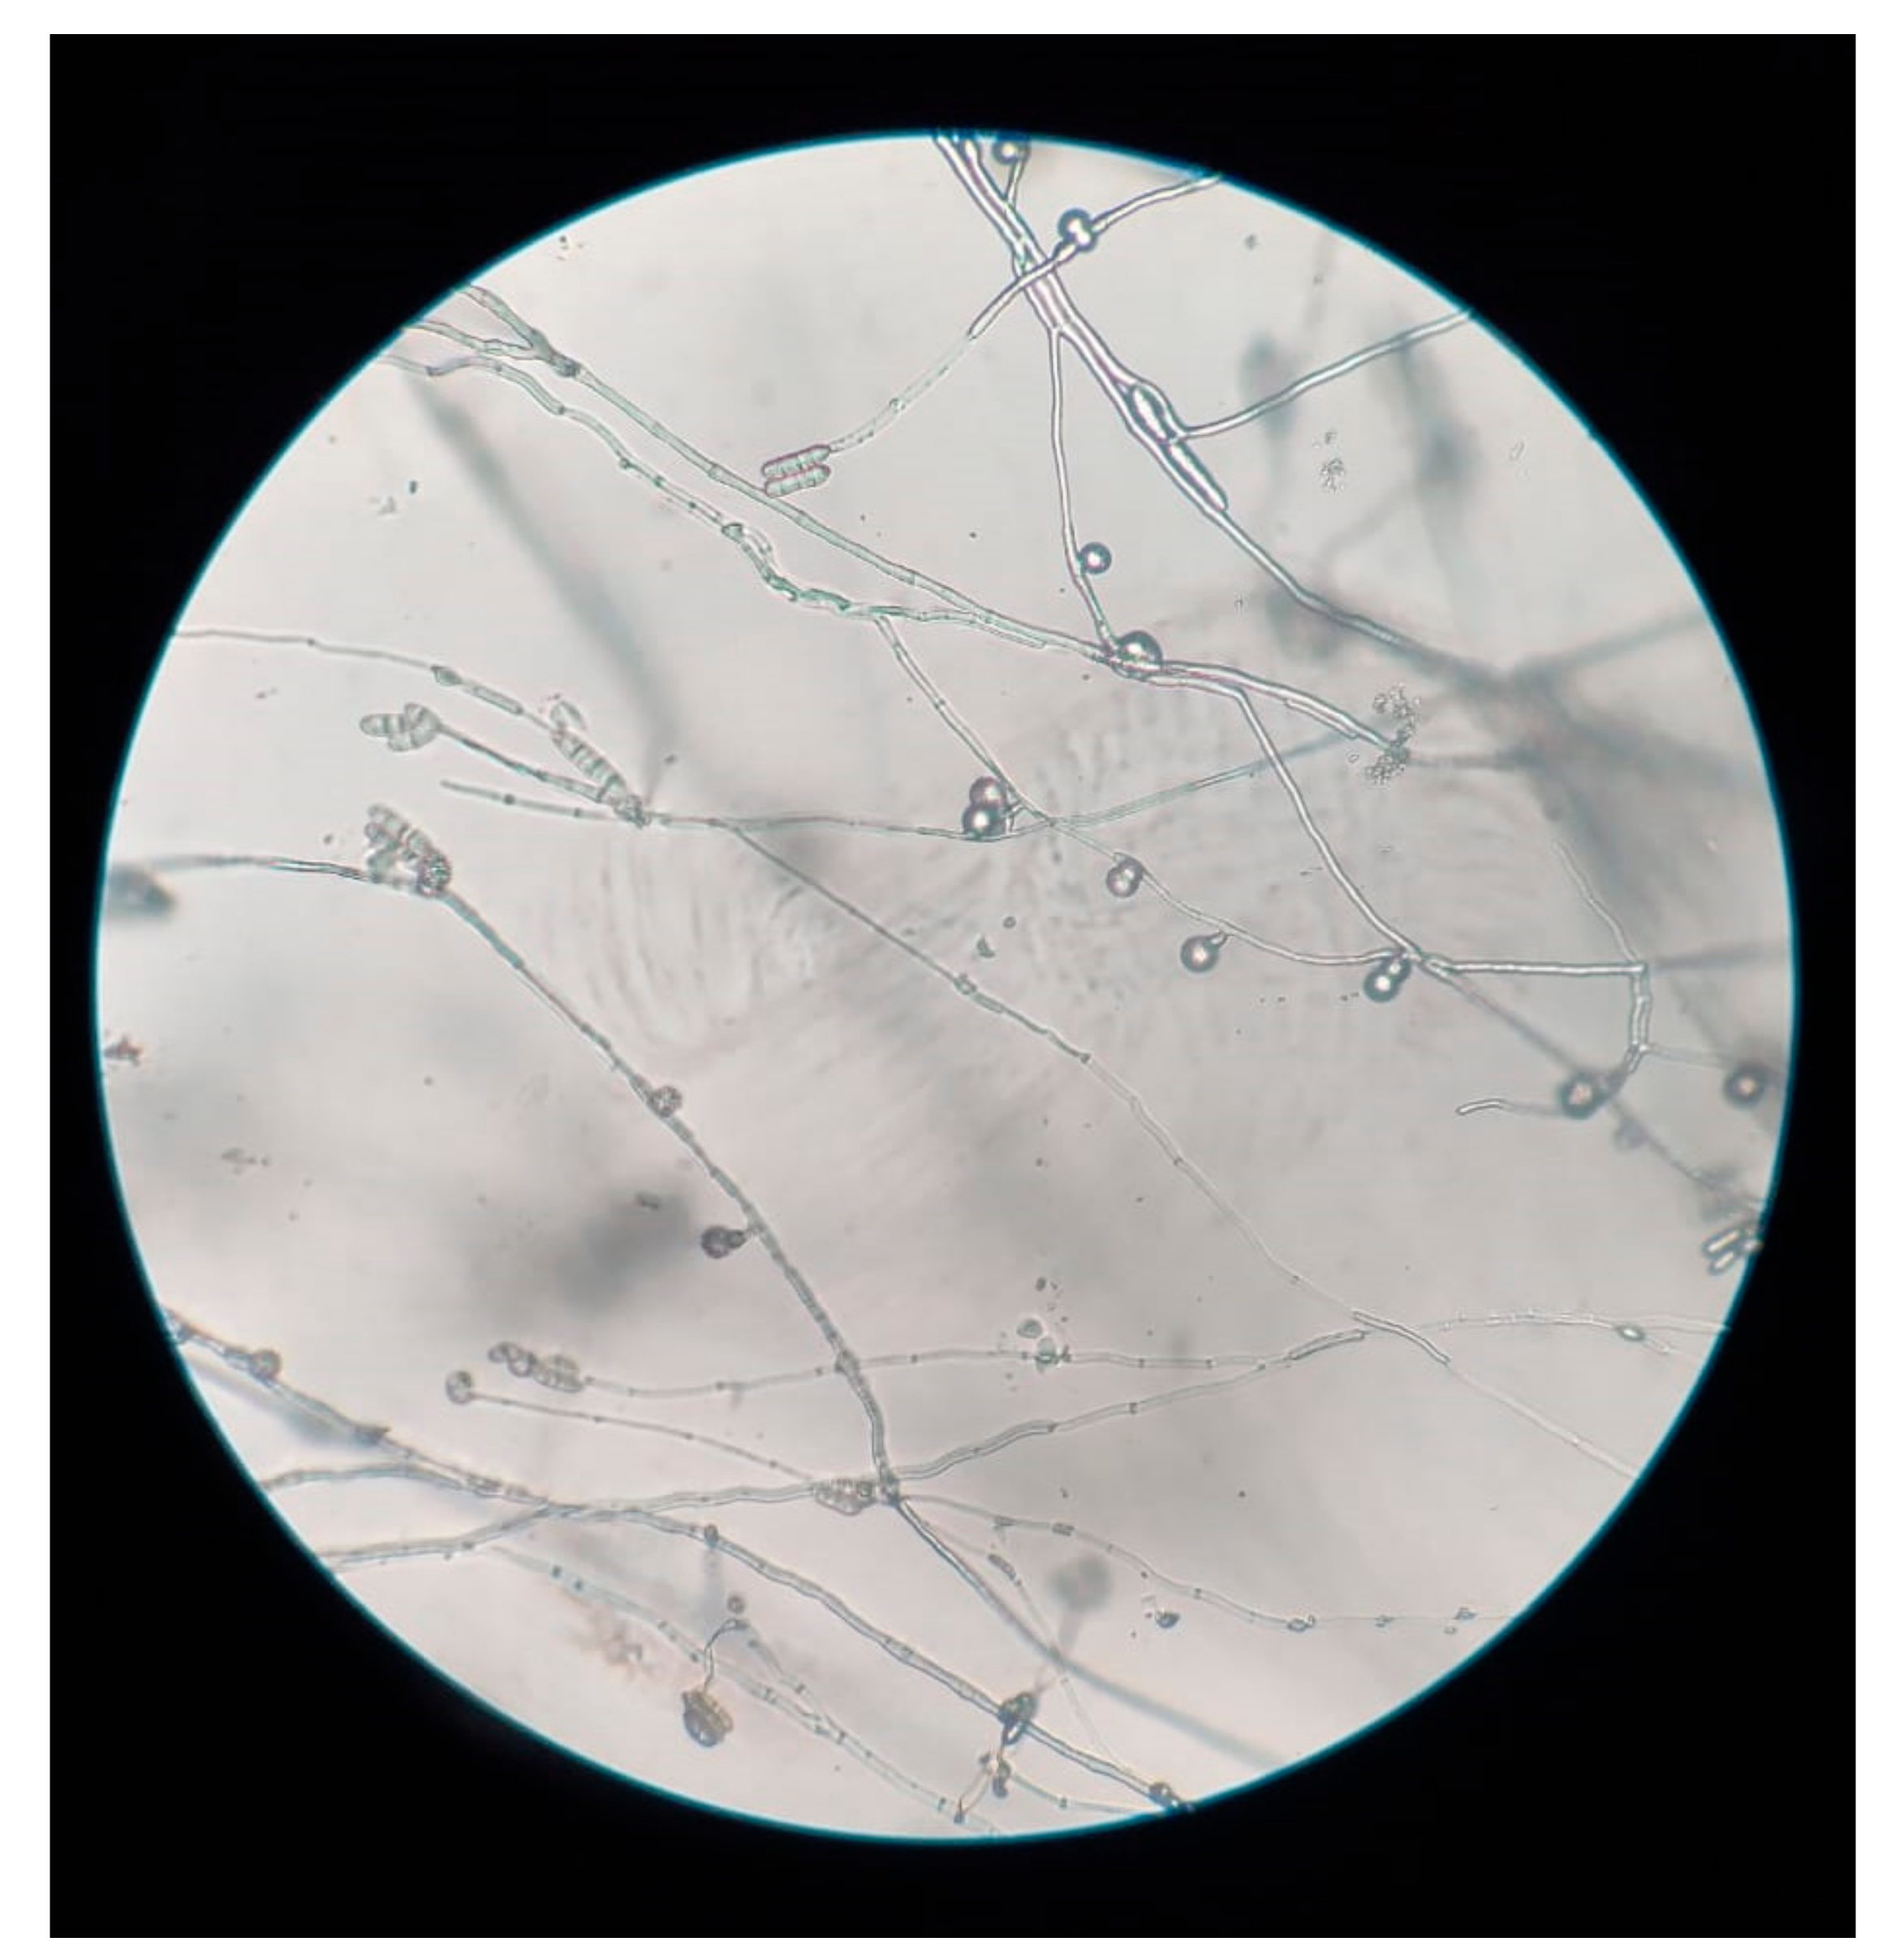

2. Case